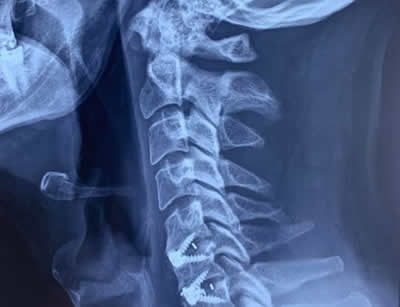

IMÁGENES

Galería de imágenes